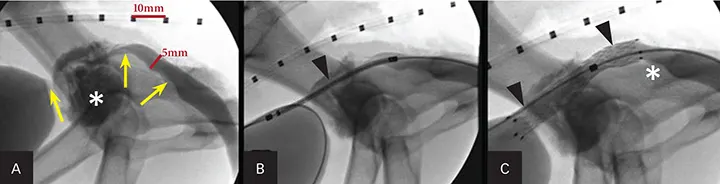

A reliable and safe alternative to establish urethral patency is placement of a self-expanding metallic stent by a transurethral approach with fluoroscopy (Figure 9). This outpatient procedure is associated with good-to-excellent palliative outcomes in more than 95% of cases. It has been successful in both dogs and cats; however, approximately 25% of patients will exhibit some urinary incontinence after stent placement.

Figure 9. Fluoroscopic images of a male dog during urethral stent placement for obstructive prostatic carcinoma (asterisk; A). Retrograde cystourethrography shows the obstructive lesion (arrows). A marker catheter is used to measure the urethral lumen diameter for stent sizing. A constrained urethral stent (arrowhead; B) is placed over a guide wire prior to deployment across the obstructive tumor. The deployed urethral stent (arrowheads; C) shows patency of the urethral lumen. There is still some tumor caudal to the stent (asterisk).

Urethral stenting has also been useful in patients with benign urethral strictures, granulomatous or proliferative urethritis, or reflex dyssynergia when traditional therapies have failed.